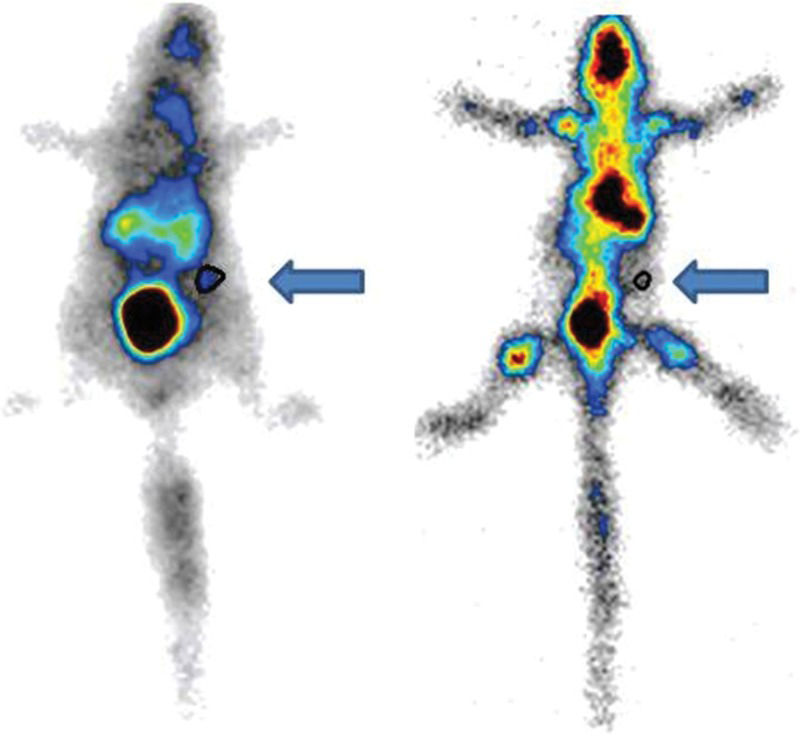

Shortly after femur grafting (baseline), tomographic imaging was performed (Figure 2).

Tomographic imaging of an animal immediately after syngeneic femur implant (upper image) and at 60 days of storage (lower image). The grafts (arrows) can be identified below the rib cage. On the 60-day image, the bone resorption is highly advanced (nearly 50% of the mass). This phenomenon did not always occur, with other animals exhibiting far less bone loss.

After each scheduled follow-up period (15, 30 and 60 days), radiotracers were injected for bone assessment. In vivo images were acquired, and subsequently, the removed bone was examined for tracer uptake and compared to the control femur. Nonradioactive grafts and orthotopic homolateral controls were surgically excised simultaneously for histological analysis. After 60 days, as mentioned above, CT imaging was also performed for comparison with baseline findings.

After 30 and 60 days, the inflammatory tissue reaction around the bone continued to occur, although less hyperemia was observed. Bone edema disappeared and was replaced by progressive brittleness and resorption. By 60 days, bone resorption and fragmentation were conspicuous, and in certain animals, as little as 50% of the original femur could be recovered from the subcutaneous pouch. Bone marrow changes suggestive of necrosis were also noted at 30 days and were more remarkable after 60 days (Figures 2 and 4).

Static images obtained with a gamma camera (Figure 8) revealed the uptake of radiotracers in the entire body and in the femur grafts after 15 days.